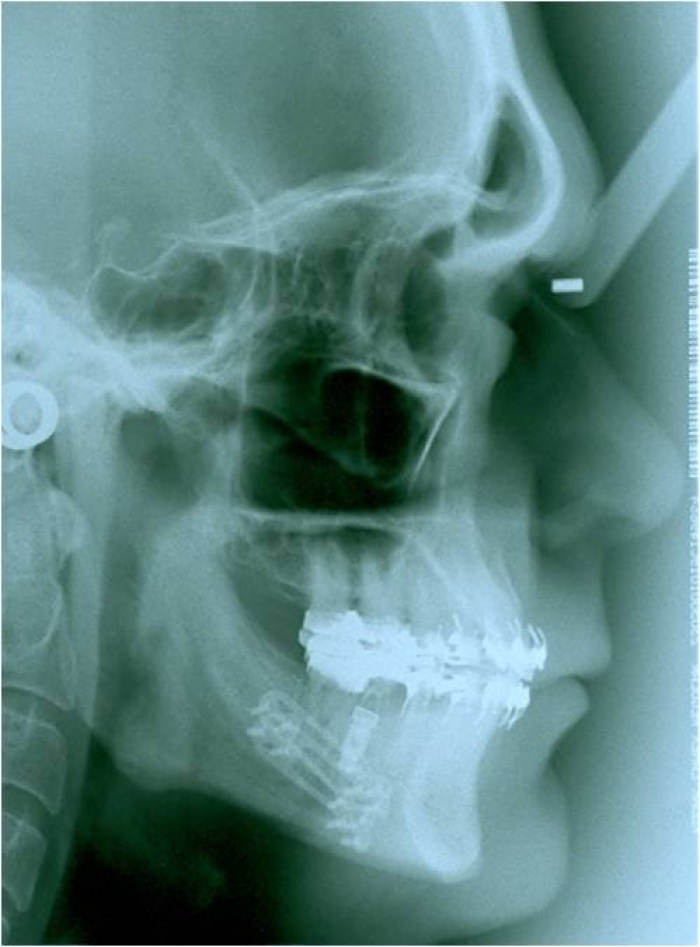

Telerradiografia inicial

Telerradiografia após a cirurgia